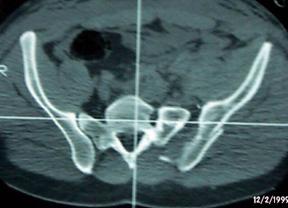

Fractura Malgaigne Fractura Malgaigne. Imagine CT

Compresie laterala

Fracturi pelviene multiple Fracturi pelviene multiple

Compresie bilaterala Compresie bilateralaAspect CT

Fracturi pelviene multiple Fracturi bilaterale de ramuri pubiene

Compresie bilaterala Aspect CT Disjunctie sacro-iliaca stanga Compresie antero-posterioara